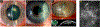

Fusarium, Aspergillus and Candida are important fungal pathogens that cause visual impairment and blindness in the USA and worldwide. This review will summarize the epidemiology and clinical features of corneal infections and discuss the immune and inflammatory responses that play an important role in clinical disease. In addition, we describe fungal virulence factors that are required for survival in infected corneas, and the activities of neutrophils in fungal killing, tissue damage and cytokine production.